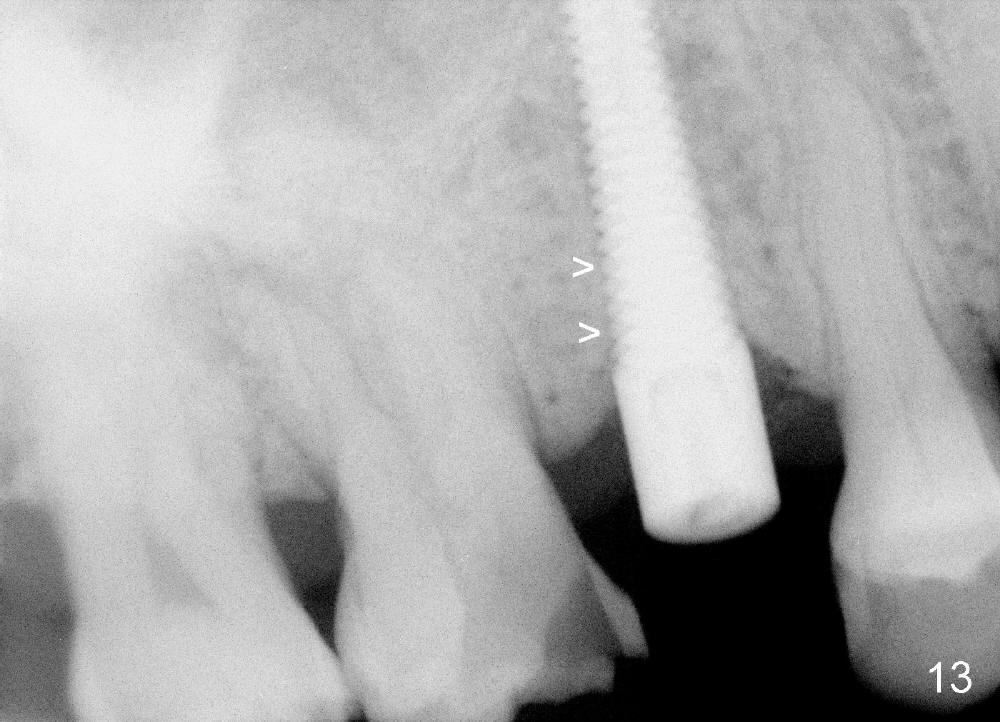

A 72-year-old man is a bruxer with #3 cusp fracture with chronic periapical radiolucency (Fig.1 *) and #4 acute crack. It appears reasonable to take care of emergency (#4 extraction and immediate implant (Fig.3-7: 4.5x20 mm, 45 Ncm)) followed by root canal therapy or extraction for #3. Eight (Fig.8) and 14 (Fig.9-11) days postop, the patient is doing fine and the wound heals normally. But he does not agree any treatment for #3, since it is asymptomatic in spite of a fistula associated with the tooth (Fig.8,9 >). Three months postop, the patient is still asymptomatic and is ready for #4 restoration since the tooth #28 cracks. Follow-up PA shows the persistent distal gap (Fig.12 >, as compared to Fig.4), accompanied with crestal bone resorption (*). Clinically the implant has mild mobility and light tenderness. The patient still refuses #3 treatment. It appears that the implant has failed to osteointegrate. In brief, do not place an immediate implant next to active infection.

Five and a half months postop, the distal gap appears to have reduced (Fig.13 >). Clinically the implant is stable and is ready for restoration. It is advisor able to watch those asymptomatic immediate implants with minimal mobility. It takes time to osteointegrate the immediate implant considering the peri-implant space.